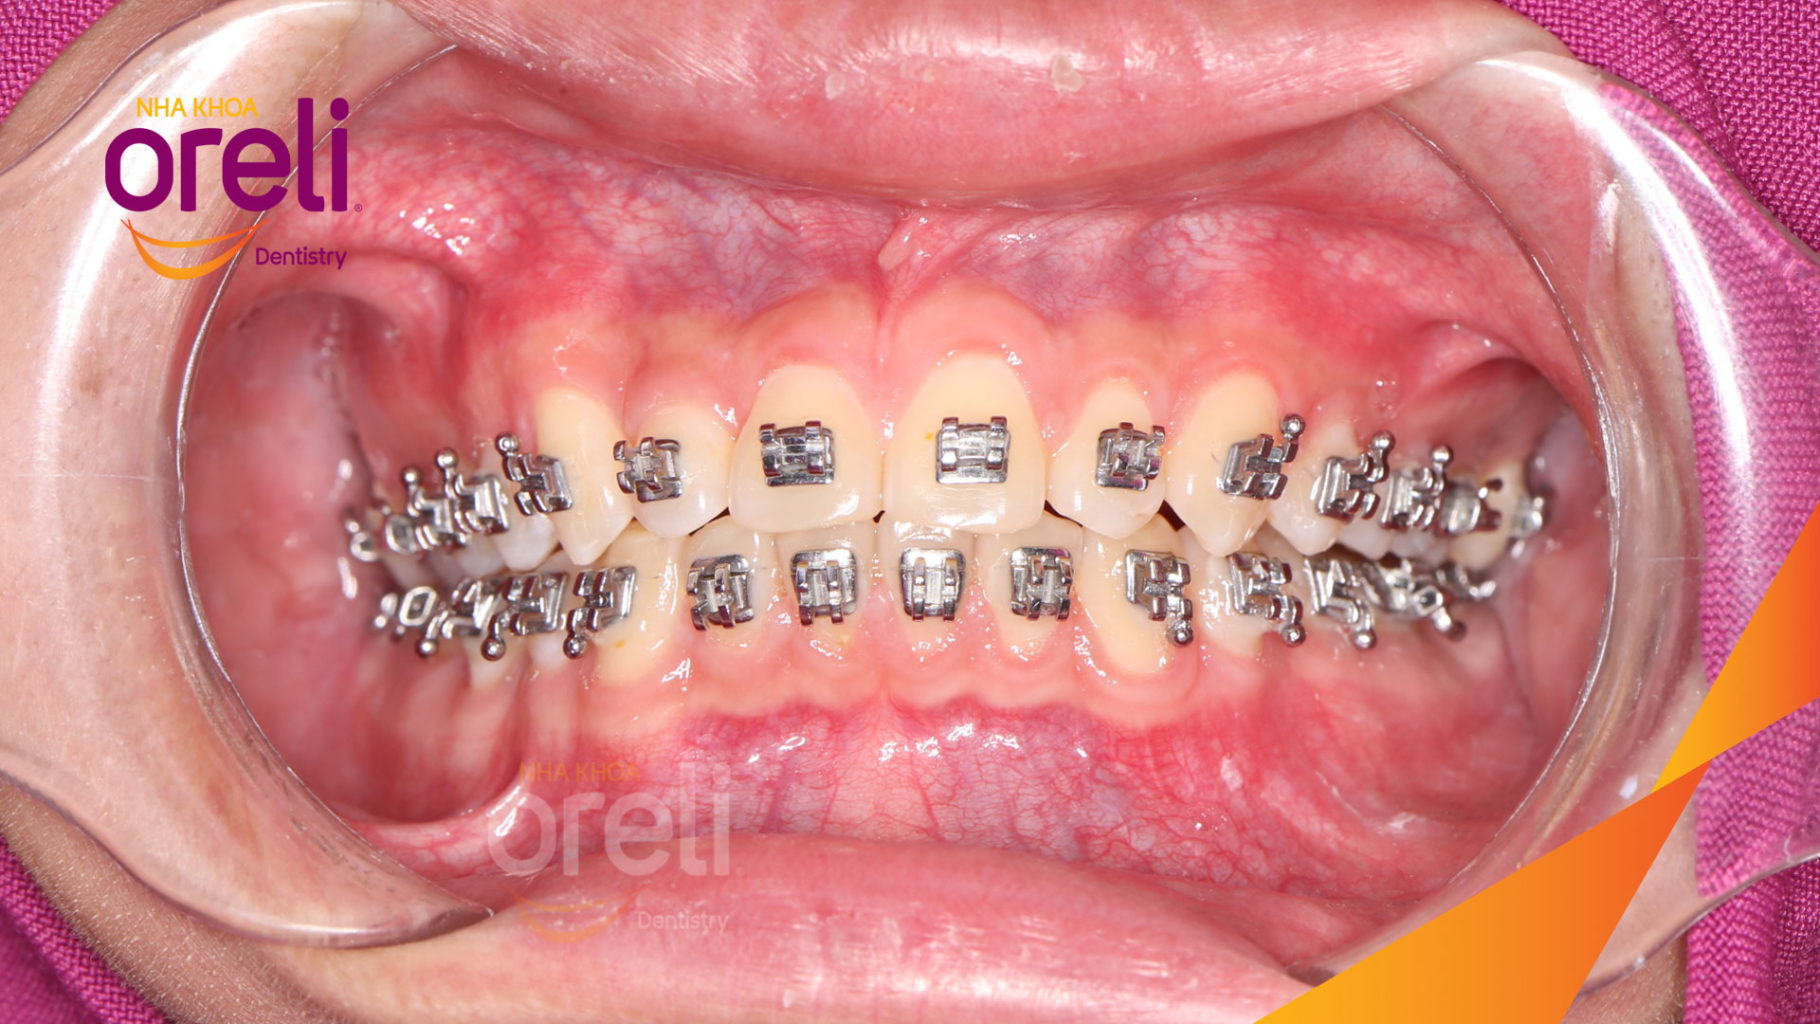

Giải pháp: làm đều chỉnh khớp cắn sâu không nhổ răng

Thời gian: 36 tháng

Kết quả: khớp cắn đúng, cằm tiến ra trước với mặt nghiêng đẹp

Hình ảnh thực tế